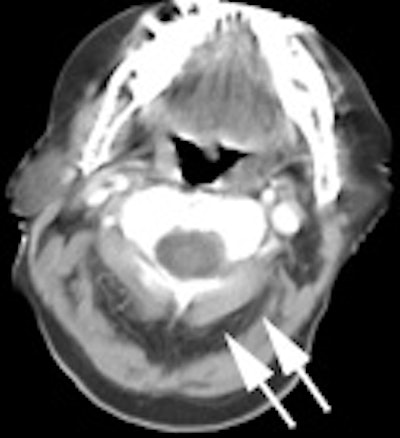

|

Head and neck activity: The images below show typical uptake in the tonsils (black arrows), submandibular glands (blue arrows), and parotid glands (red arrows) |